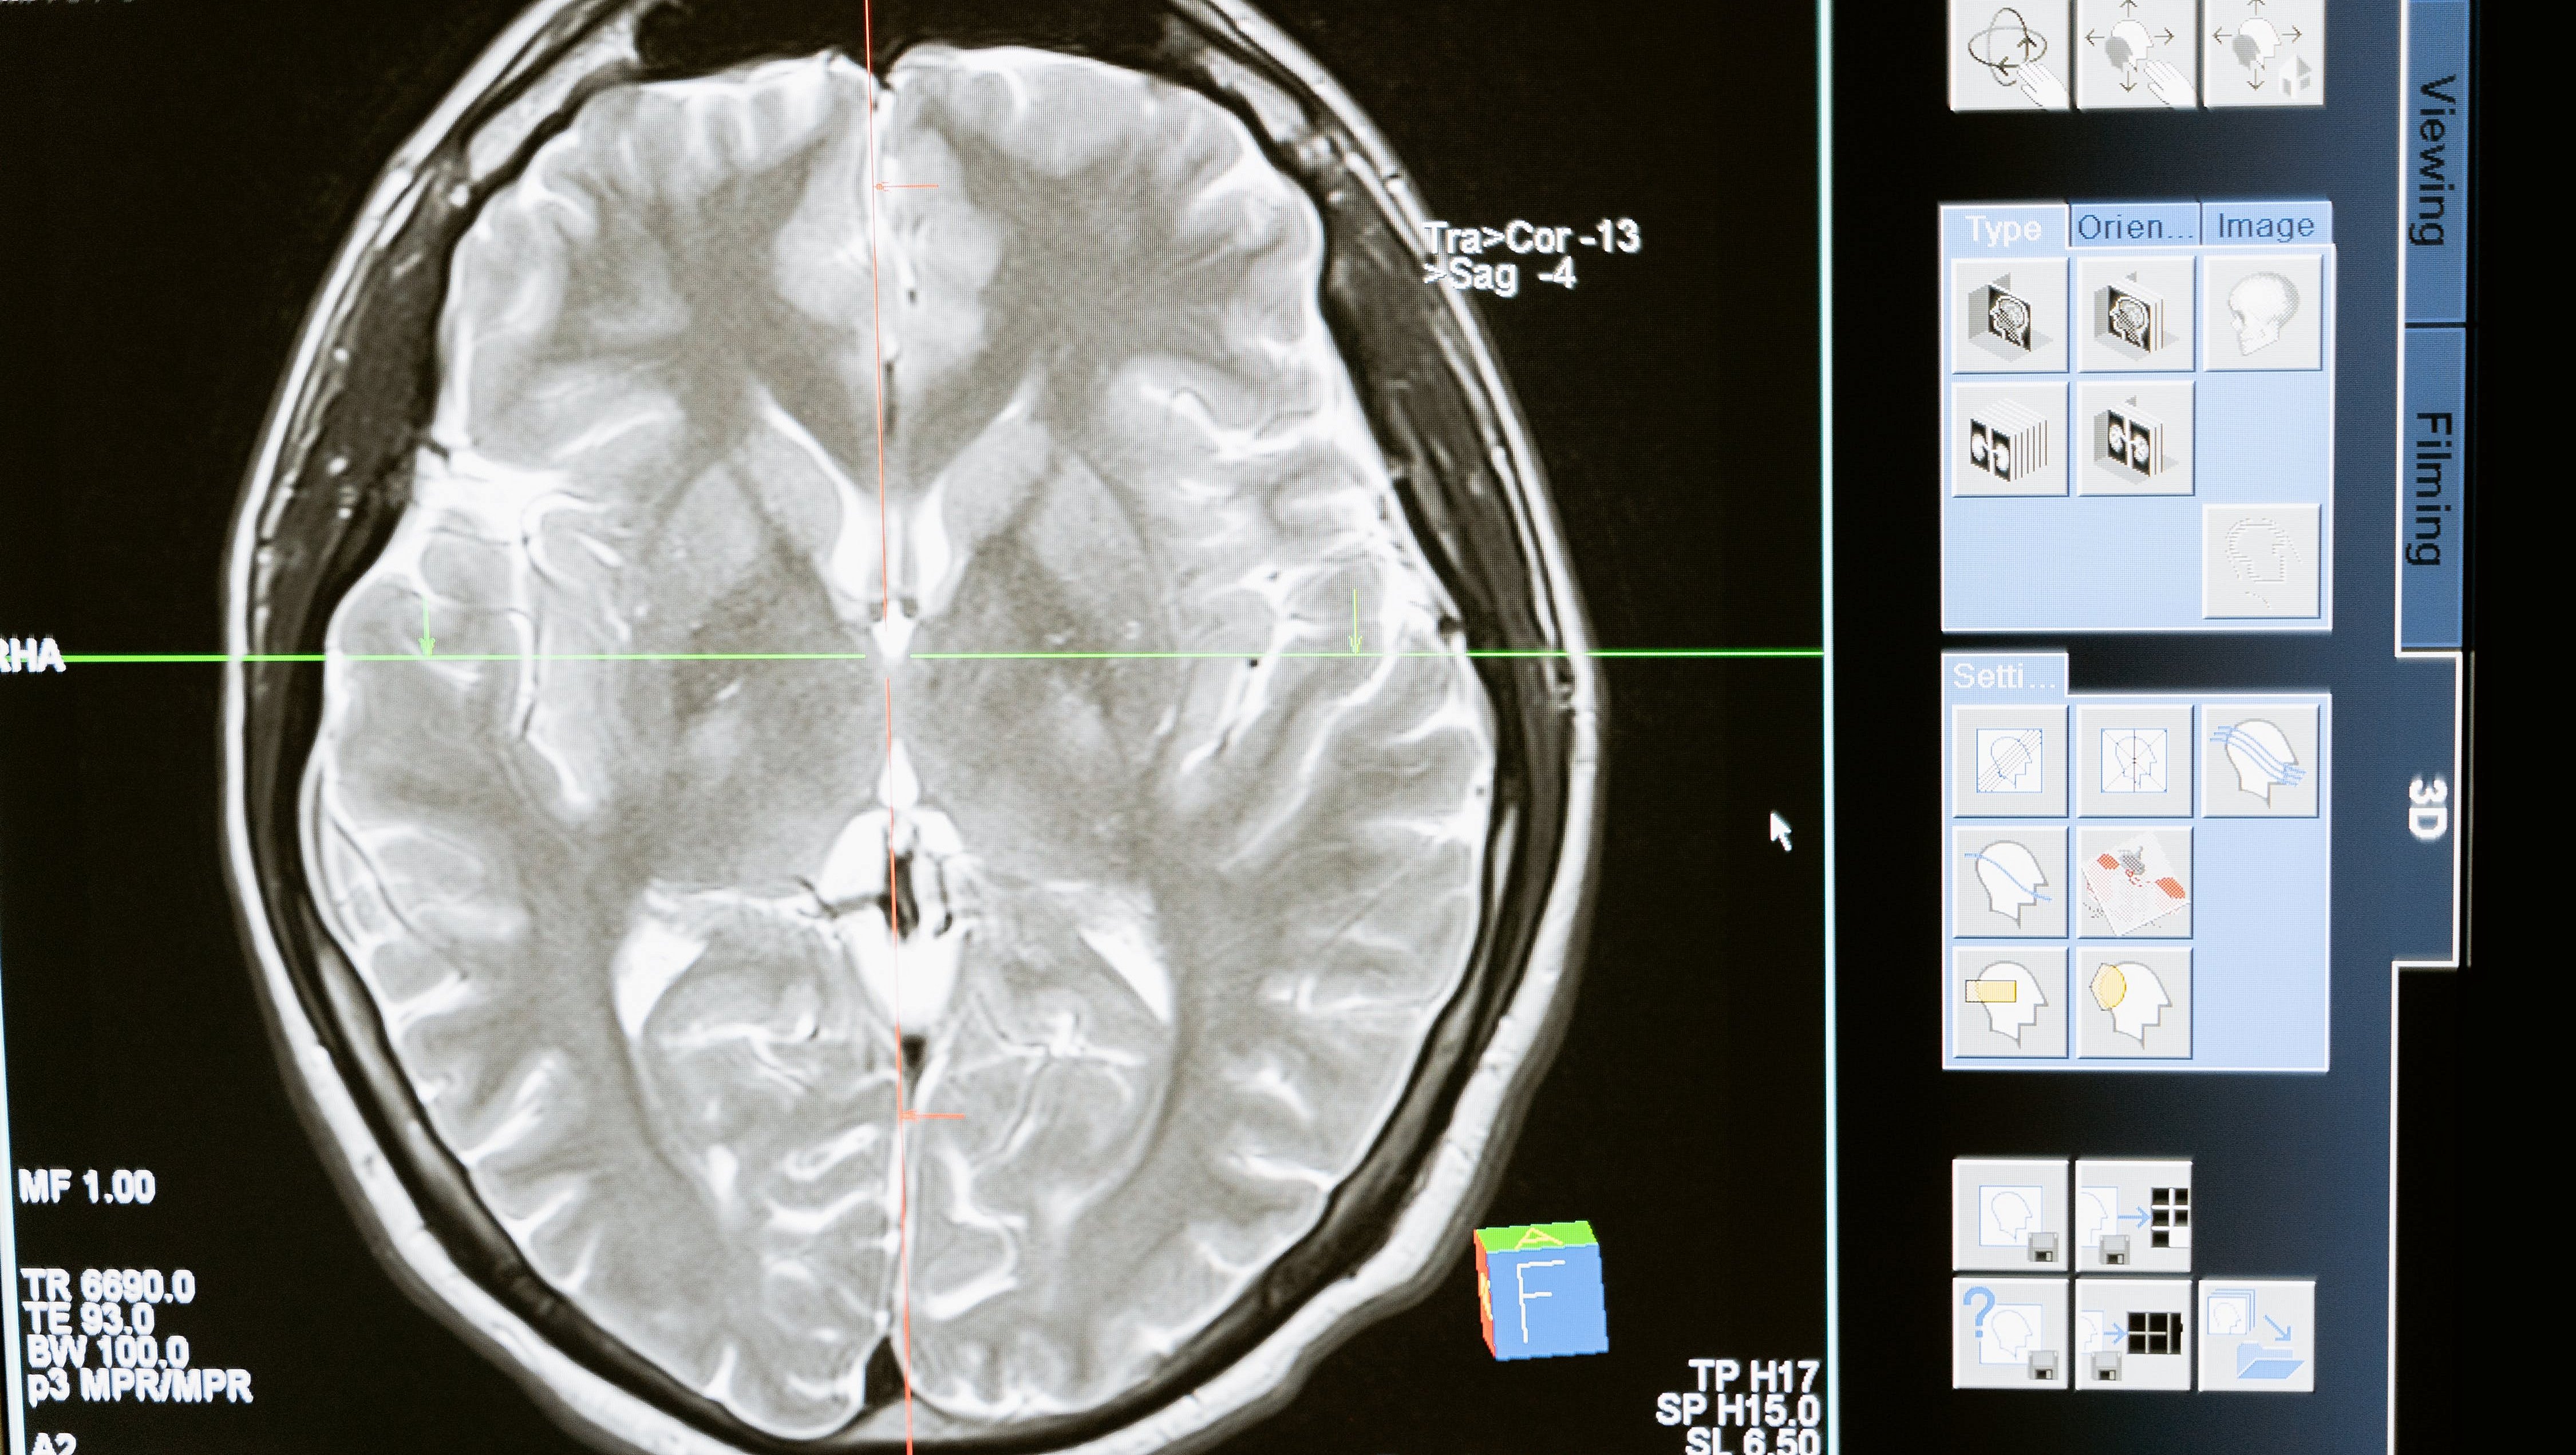

Spinoserebellar Ataksi Tip 2 Hastalarının Beyinlerinde Poliglutamin ve Transaktivasyona Duyarlı DNA Bağlayıcı Protein 43'ün Paralel Görünümü ve Tamamlayıcı Subselüler Lokalizasyonu

Kaynak: https://academic.oup.com/jnen/article-abstract/81/7/535/6576841?redirectedFrom=fulltext . Spinoserebellar ataksi tip 2 (SCA2), ATXN2'deki mutasyonlardan kaynaklanır.Ataksin-2 içindeki genişletilmiş poliglutamin tekrarları tarafından toksik etkilerin tetiklendiği gen. SCA2'ye, amyotrofik lateral sklerozda (ALS) olduğu gibi motor nöron dejenerasyonu eşlik eder. 3 SCA2 hastasının CNS'sinde ataksin-2 ve ALS'de hastalıkla ilgili önemli bir protein olan transaktivasyona duyarlı DNA bağlayıcı protein 43'ün (TDP-43) dağılım modellerini araştırdık. Fosforillenmiş TDP-43 (pTDP-43)-pozitif lezyonlar, CNS'de geniş çapta dağılmıştı ve genellikle 1C2 (genişletilmiş poliglutamin)-immünoreaktif lezyonlarla örtüşüyordu. Bu dağılım paterni, limbik baskın yaşa bağlı TDP-43 ensefalopatideki paternden farklıdır. SCA2'de, motor nöronlarda TDP-43 ve 1C2'nin çift immün boyaması, 3 boyama modeli ortaya çıkardı: sitoplazmik 1C2 ve nükleer TDP-43, nükleositoplazmik 1C2 ve nükleer TDP-43, ve sırasıyla patolojik değişimin erken, aktif ve son aşamalarını yansıtan nükleer 1C2 ve sitoplazmik TDP-43. TDP-43'ün çekirdekten sitoplazmaya ve 1C2'nin ters yönde yer değiştirmesi, hastalığa özgü protein ataksin-2'nin nükleer birikiminin TDP-43'ün hücre içi dinamiklerini etkilediğini gösterir. Hücredeki mutant ataksin-2 ve TDP-43 arasındaki bu kadar yakın bir ilişki, SCA2'li hastaların CNS'sindeki dağılımlarının benzerliğini açıklayabilir. TDP-43'ün çekirdekten sitoplazmaya ve 1C2'nin ters yönde yer değiştirmesi, hastalığa özgü protein ataksin-2'nin nükleer birikiminin TDP-43'ün hücre içi dinamiklerini etkilediğini gösterir. Hücredeki mutant ataksin-2 ve TDP-43 arasındaki bu kadar yakın bir ilişki, SCA2'li hastaların CNS'sindeki dağılımlarının benzerliğini açıklayabilir. TDP-43'ün çekirdekten sitoplazmaya ve 1C2'nin ters yönde yer değiştirmesi, hastalığa özgü protein ataksin-2'nin nükleer birikiminin TDP-43'ün hücre içi dinamiklerini etkilediğini gösterir. Hücredeki mutant ataksin-2 ve TDP-43 arasındaki bu kadar yakın bir ilişki, SCA2'li hastaların CNS'sindeki dağılımlarının benzerliğini açıklayabilir.